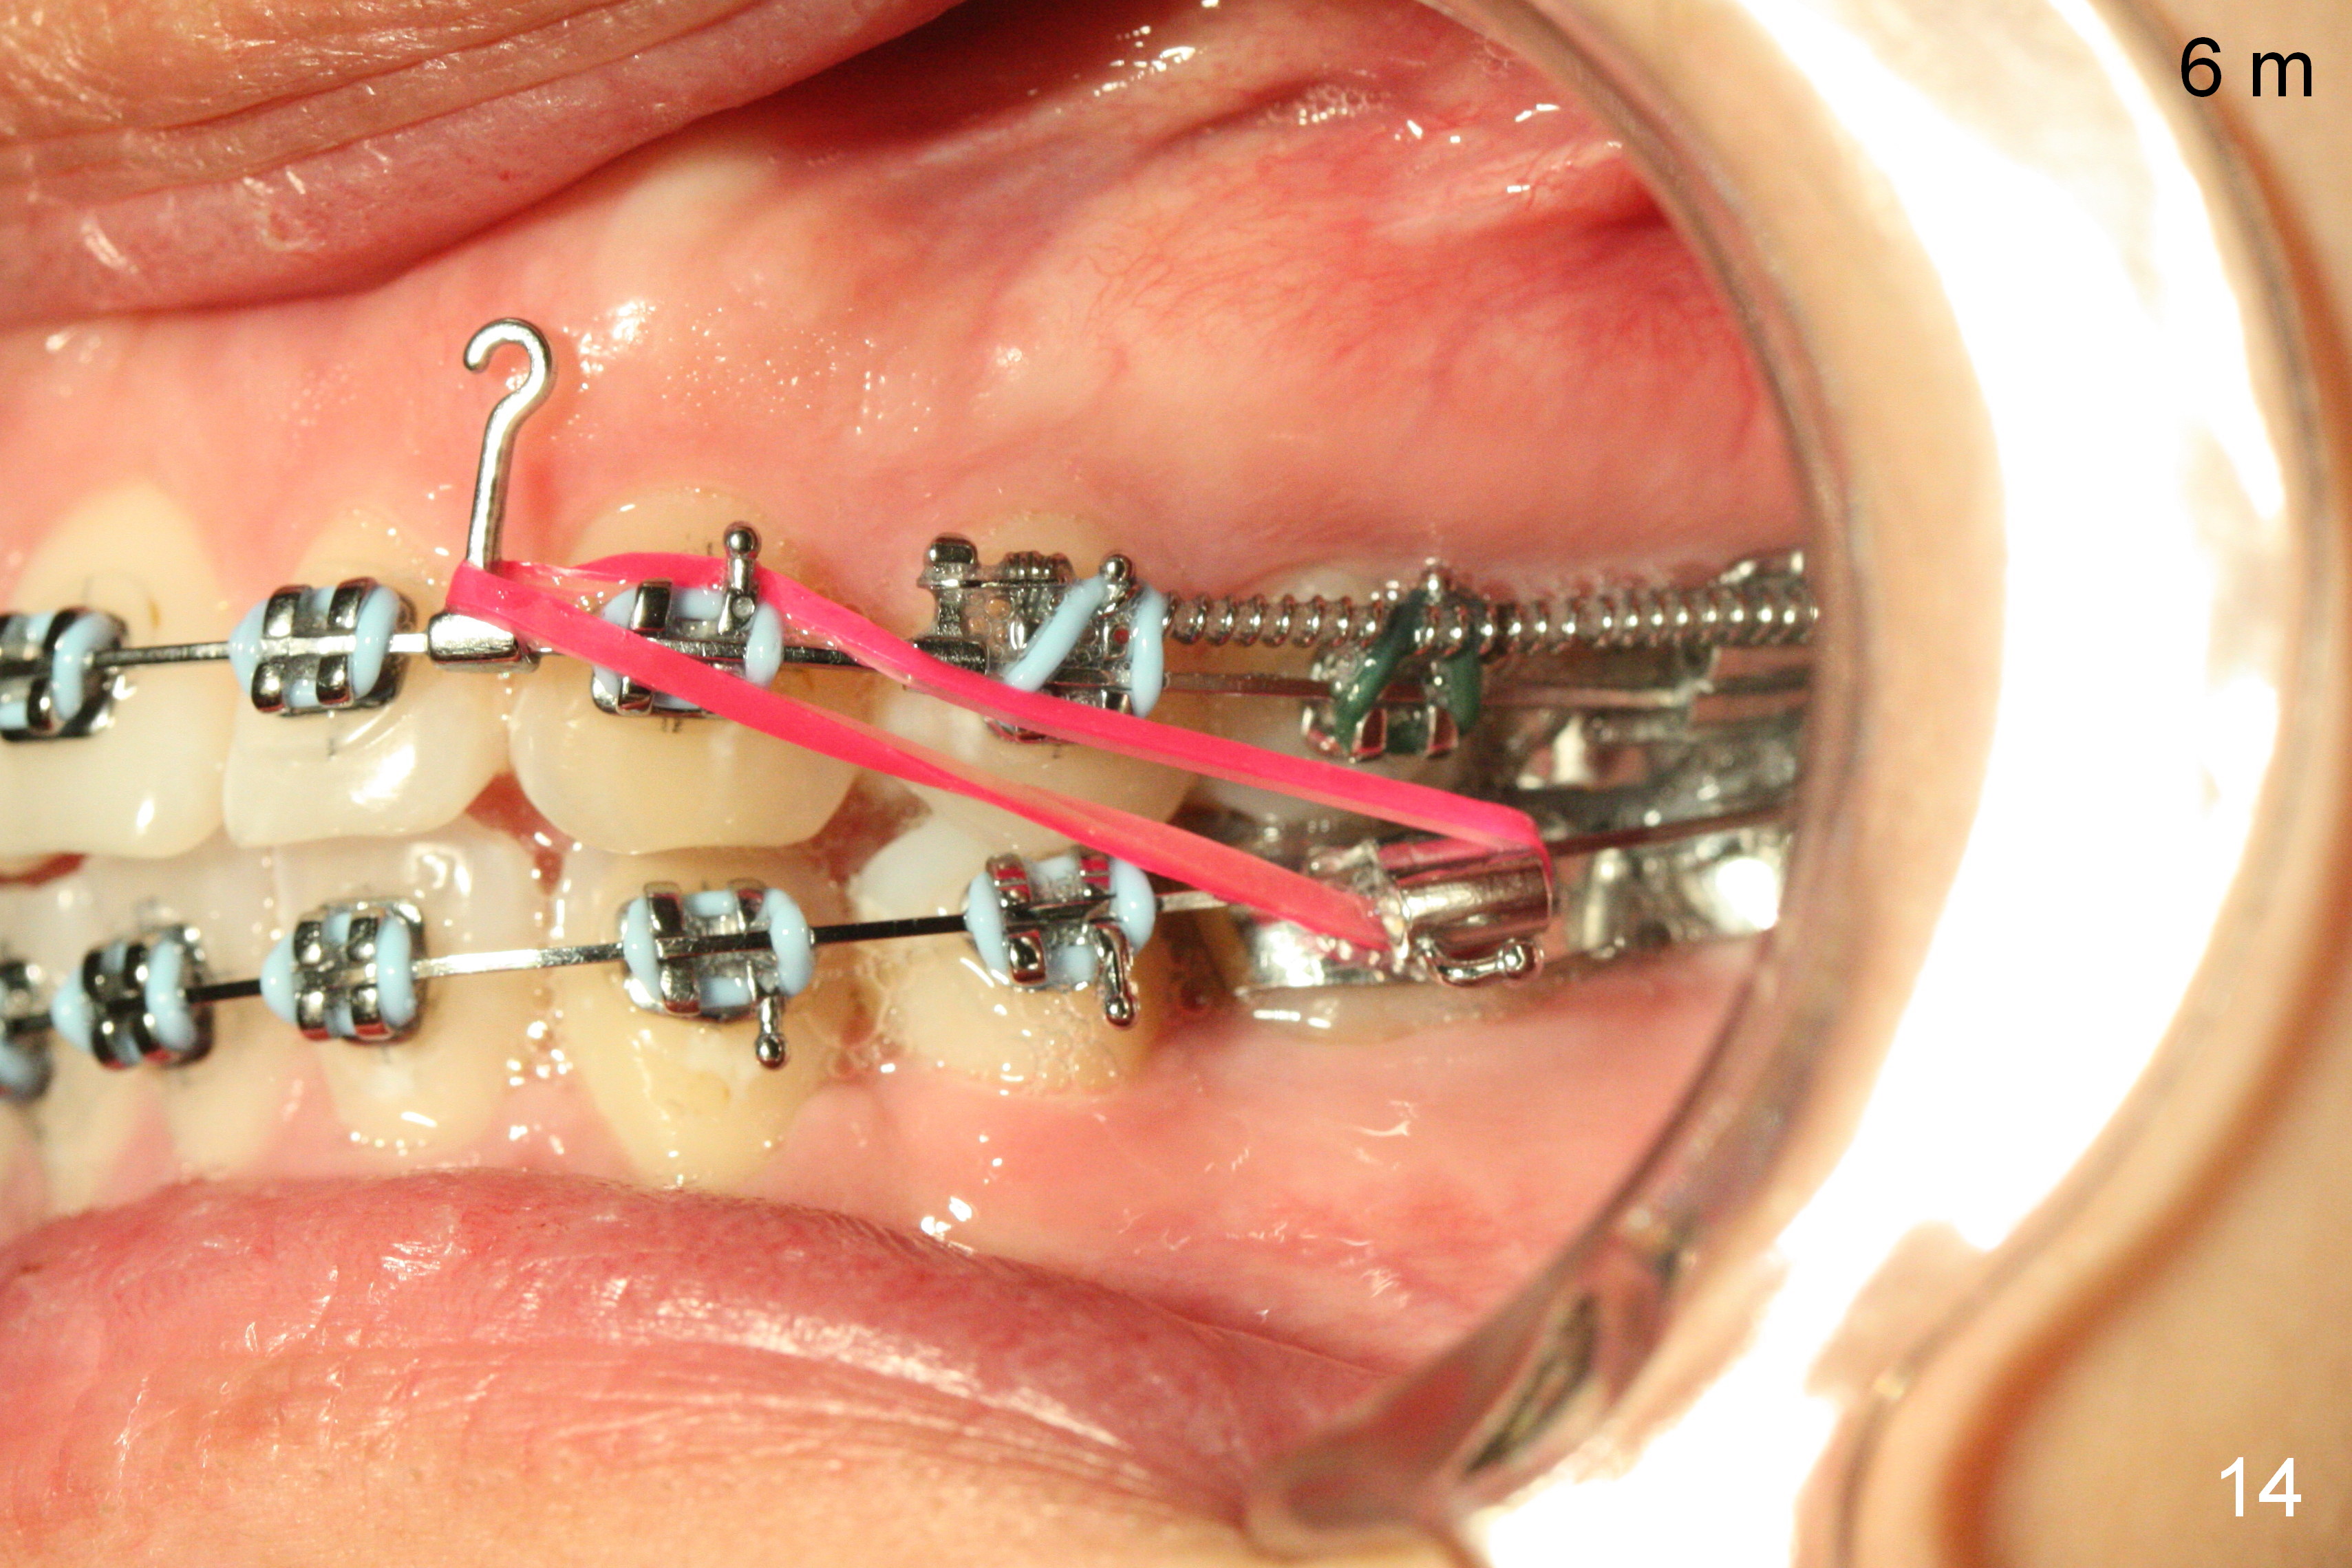

Six months post zygomatic implants, the profile, anterior overbite and overjet and the right posterior interdigitation are within normal limit (Fig.11), whereas the left one not (Fig.12).  The lower midline appears to be deviated to the left.  Elastics are used for correction (Fig.11,13,14).  A second option is to reduce the number of closed springs on the right and increase the one on the left.